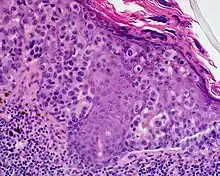

Lentigo maligna melanoma is a melanoma that has evolved from a lentigo maligna,[1]: 695 as seen as a lentigo maligna with melanoma cells invading below the boundaries of the epidermis.[2] They are usually found on chronically sun damaged skin such as the face and the forearms of the elderly.

Lentigo maligna is the non-invasive skin growth that some pathologists consider to be a melanoma-in-situ.[3] A few pathologists do not consider lentigo maligna to be a melanoma at all, but a precursor to melanomas. Once a lentigo maligna becomes a lentigo maligna melanoma, it is treated as if it were an invasive melanoma.

An invasive tumor arising from a classical lentigo maligna. Usually a darkly pigmented raised papule or nodule, arising from a patch of irregularly pigmented flat brown to dark brown lesion of sun exposed skin of the face or arms in an elderly patient.